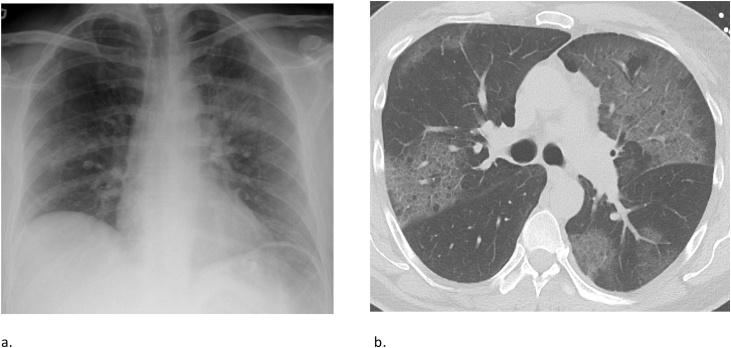

Pulmonary edema is a common clinical entity caused by the extravascular movement of fluid into the pulmonary interstitium and alveoli. The four physiologic categories of edema include hydrostatic pressure edema, permeability edema with and without diffuse alveolar damage (DAD), and mixed edema where there is both an increase in hydrostatic pressure and membrane permeability. As radiographic manifestations and etiologies are varied, an appreciation for both the common and uncommon manifestations and causes of pulmonary edema is essential for accurate diagnosis.

肺水肿是一种常见的临床病症,由液体向肺间质和肺泡的血管外移动所致。水肿的四种生理类型包括静水压性水肿、伴有或不伴有弥漫性肺泡损伤(DAD)的通透性水肿,以及静水压和膜通透性均增加的混合性水肿。由于影像学表现和病因各不相同,了解肺水肿的常见和不常见表现及病因对于准确诊断至关重要。